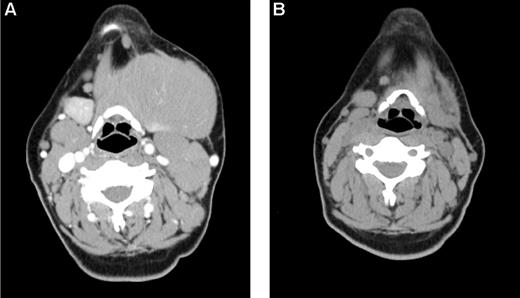

Early response in bulky, chemoresistant lymphoma. A 33-year-old woman with CLL/SLL had a partial response lasting 10 months after initial therapy with 6 cycles of fludarabine-R and then experienced progressive disease while receiving pentostatin-cyclophosphamide-R, and continued progressive disease while receiving CHOP. (A) Baseline image reveals a dominant 12 cm left submandibular mass. She was treated with 32 mCi of 90Y-ibritumomab tiuxetan, fludarabine, 2 Gy TBI, and a matched unrelated allogeneic transplant and achieved a PR by after transplantation day 28 (B) and complete remission by day 84. The patient remains alive and disease-free 3 years after transplantation.